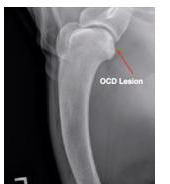

Being quite a large breed they tend to experience problems with their joints and bones as they have to support a lot of weight. Some of these include hip dysplasia and osteoarthritis. To help this, they can be provided with joint supplements such as glucosamine. Another concern is osteochondritis dissecans (OCD), this is a condition that affects the cartilage in the joints. This condition causes a flap of cartilage to form in the joint which can cause a painful inflammatory response. Typically to manage this condition your puppy will be put on pain meds and will probably have exercise restrictions. If your puppy is six months old or older they will most likely need surgery to help.

Example of OCD Lesion from Veterinary Partner Journal